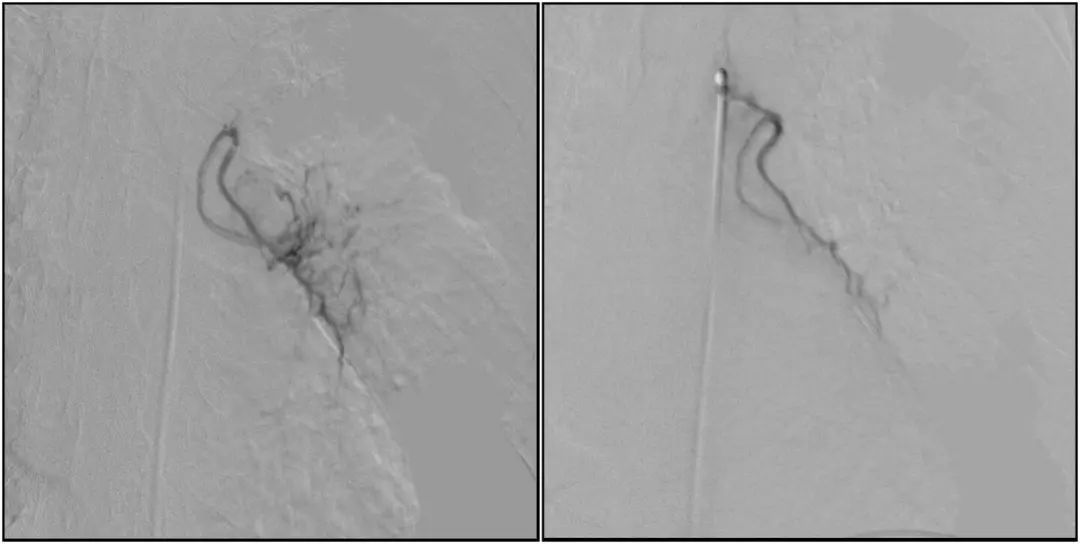

支氣管動脈栓塞+化療灌注術(shù)

在普愛醫(yī)療移動式平板介入中C影像的引導下,醫(yī)生為患者實施雙側(cè)支氣管動脈栓塞+化療灌注術(shù)。

在微導絲的配合下,先后分別超選擇①至3支左側(cè)支氣管動脈腫瘤供血動脈,經(jīng)微導管推注栓塞微粒球栓塞腫瘤動脈。栓塞結(jié)束后,再次用移動式平板介入中C做造影檢查,見腫瘤染色消失。

術(shù)前術(shù)后對比影像